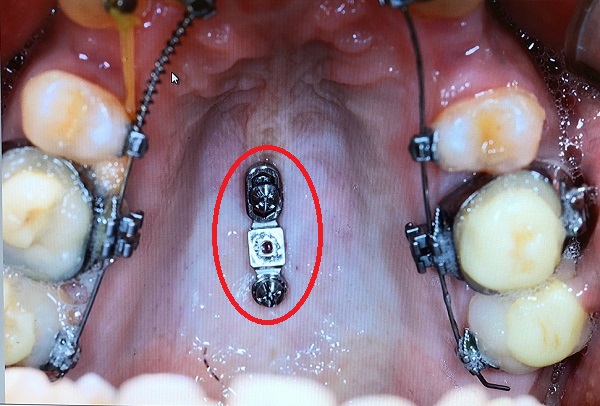

矯正用のインプラントは↓こちらのようなもの。アンカーインプラントとも呼びます。

今回はインプラントを打ち込んだのみで、両側の歯との接続は行っていません。

今回は口蓋につけたインプラントの役目になります。